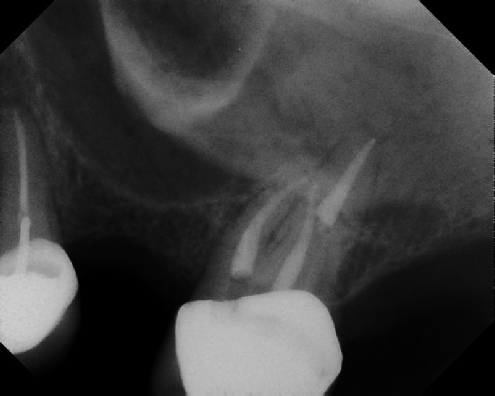

Root Canal Retreatment - Meriden 8 mos. recall Post-op Pre-op